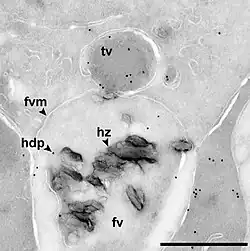

The malaria parasite, therefore, detoxifies the hematin, which it does by biocrystallization—converting it into insoluble and chemically inert β-hematin crystals (called hemozoin).[13][14][15] In Plasmodium the food vacuole fills with hemozoin crystals, which are about 100–200 nanometres long and each contain about 80,000 heme molecules.[4] Detoxification through biocrystallization is distinct from the detoxification process in mammals, where an enzyme called heme oxygenase instead breaks excess heme into biliverdin, iron, and carbon monoxide.[16]

Several mechanisms have been proposed for the production of hemozoin in Plasmodium, and the area is highly controversial, with membrane lipids,[17][18] histidine-rich proteins,[19] or even a combination of the two,[20] being proposed to catalyse the formation of hemozoin. Other authors have described a heme detoxification protein, which is claimed to be more potent than either lipids or histidine-rich proteins.[12] It is possible that many processes contribute to the formation of hemozoin.[21] The formation of hemozoin in other blood-feeding organisms is not as well-studied as in Plasmodium.[22] However, studies on Schistosoma mansoni have revealed that this parasitic worm produces large amounts of hemozoin during its growth in the human bloodstream. Although the shapes of the crystals are different from those produced by malaria parasites,[23] chemical analysis of the pigment showed that it is made of hemozoin.[24][25] In a similar manner, the crystals formed in the gut of the kissing bug Rhodnius prolixus during digestion of the blood meal also have a unique shape, but are composed of hemozoin.[26] Hz formation in R. prolixus midgut occurs at physiologically relevant physico-chemical conditions and lipids play an important role in heme biocrystallization. Autocatalytic heme crystallization to Hz is revealed to be an inefficient process and this conversion is further reduced as the Hz concentration increases.[27]